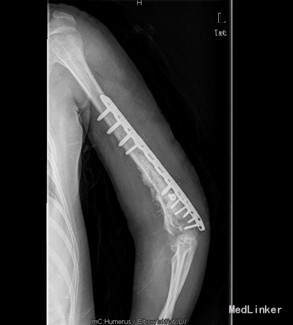

初步诊断:1、左肱骨骨折术后骨不愈合。2、左肩、左肘关节活动障碍 诊疗计划:择期行左肱骨髓内钉取出术、左肱骨骨折钢板螺钉内固定术,人工骨植骨。

术中见肱骨下份原骨折处软组织肿胀,瘢痕形成较多,有少量骨痂生成,能见原骨折端。取出髓内钉及固定钢丝后,骨折明显不稳定有假关节活动。未见明显炎性增生、渗出及坏死组织。并取随内及骨折周围部分组织送病检及培养。